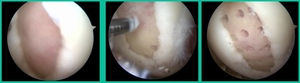

I thought I might be able to fix it. I had the conversation with the family, get in there, started taking it apart with a Vanguard elevator grasper. Behold, it’s really just cartilage fragments (Figure 2).

There’s two or three of them. We debrided it. It felt normal in six weeks, no complaints in three years. What are the results of juvenile debridement? They’re actually profoundly good. You would never expect this in the scheme of things, but the natural history of removing the piece is actually very good in the juvenile patient. However, once again, fix it if you can. Debride it, if you can’t. If they get symptoms, we restore it, and then never leave unstable fragments.

Oddly, this patient had posterior knee pain. I gave him a lidocaine injection because I couldn’t figure out what was going on. He got relief and I said, “Look, something’s going on in the joint. The only thing you got is this trochlear thing.” It was a piece of cartilage. This is all it was.

You can actually, in a young person, get cartilage to heal with no bone on it, and we use compression suture fixation (Figure 6). In his follow-up, five months after undergoing suture fixation of lateral trochlear OCD, he had a little squeaking in the knee because of the sutures there. That actually went away in time. Maybe the sutures ruptured. But he had a squeaking knee for about three months, and then that went away. So, you can fix an all-cartilage problem using a suture compression technique.